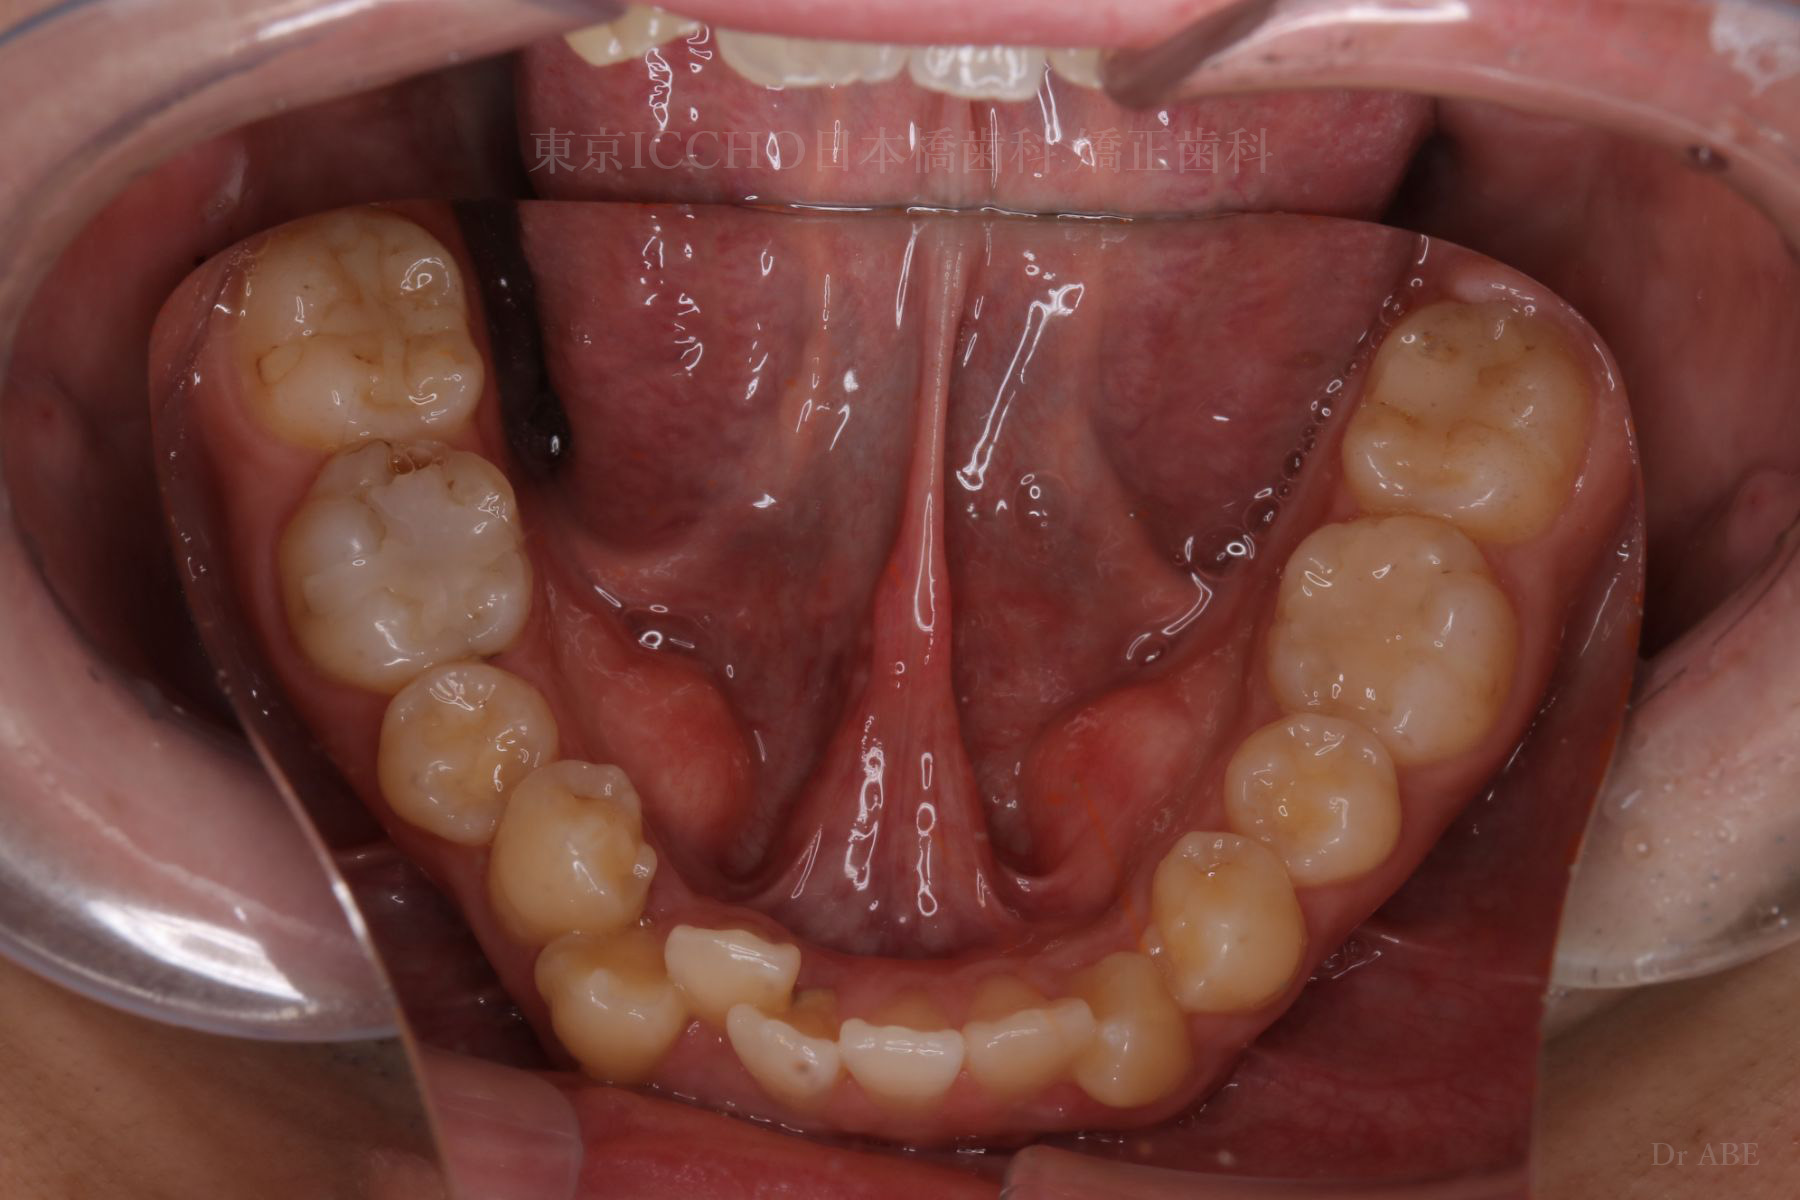

治療前

主訴 前歯が噛めないこと、出ているのを直したい。

治療内容 かみ合わせの不正と顎が小さいため、上下左右第一小臼歯4本の抜歯を行い前歯を後ろへ下げた。

また、前歯が噛まない状態のため、かみ合わせを少し下げて噛むように誘導し、全体的にかみ合わせとして機能的な矯正治療を行った。